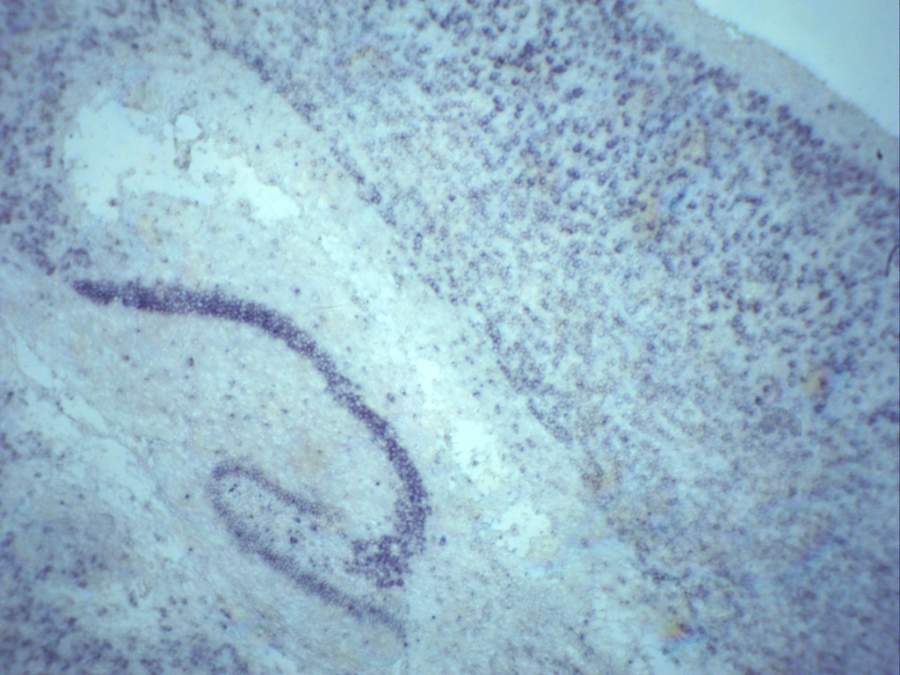

求助小鼠脑冰冻切片原位杂交